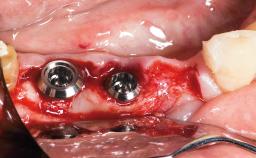

Replacement of a Maxillary Right Second Premolar Using an Early Loading Protocol

In February 2002, a 31-year-old non-smoking male patient was referred by his dentist after the fracture of the crown of the maxillary right second premolar, tooth 15. The fracture line was located apically to the gingival margin, particularly on the palatal side. Radiographic examination revealed the presence of a previous endodontic treatment with a non-ideal apical seal. There were no signs of periapical osteolysis. The level of the interproximal bone was normal. The patient’s medical history did not reveal any significant findings and he was in good general health.